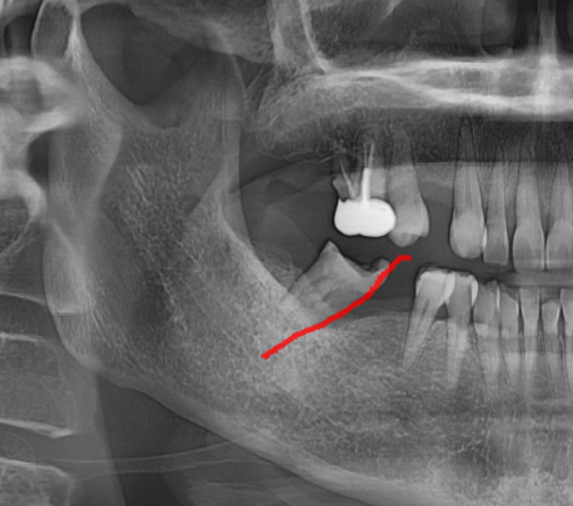

240423

문제는 육안으로 볼 때에는

티가 안납니다.

환자분은 그럭저럭 씹을 수도 있어서

문제가 없다 생각하시지만

x-ray를 찍어보면...

이만큼 기울어져있답니다.

적당히 기울어졌으면 신경치료를 하고 치아를 깎는다거나

치아를 살려볼 수 있겠으나

이정도로 치아 쓰러짐 발생하면

뽑고 임플란트를 해야합니다..